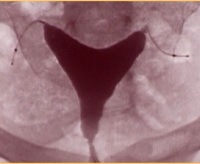

Гистероскопическая стерилизация эссюре. Современный нехирургический метод необратимой контрацепции. Это альтернатива лапароскопической или лапаротомной перевязке маточных труб. Он состоит из установки микроимплантатов (гибких пружин, состоящих из волокон титана, никеля и полиэстера) в маточных трубах. Полиэфирные волокна спиралей Essure взаимодействуют с тканями тела, стимулируя рост фиброзной ткани, которая полностью закупоривает трубу и предотвращает проникновение яйца в полость матки. Эффективность методики превышает 99%. Имплантаты Essure вводятся через влагалище в полость матки, а затем в маточные трубы. Процедура проводится без разрезов на коже под местной анестезией. Период восстановления занимает два-три дня.

После завершения установки Essure пациентка доставляется в палату, где она находится в течение 45-60 минут. Затем пациенту разрешается идти домой. Средняя продолжительность периода инвалидности после стерилизации Essure составляет 2 дня. В течение 3-4 дней может появиться небольшое кровотечение. Возобновление половой жизни возможно после полного прекращения секреции. В течение 3 месяцев после установки имплантатов Essure вы должны использовать предписанные специалистом продукты для предотвращения беременности. Затем пациент отправляется на гистеросальпингографию. После подтверждения полной окклюзии маточных труб контрацепция отменяется.